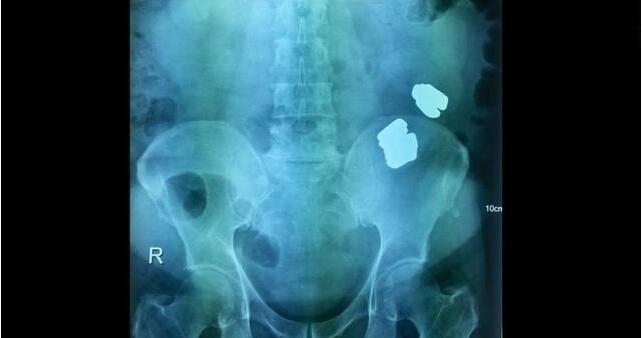

如何吞下去的啊?误食或吸入异物非常危险,需要尽快到医院寻求帮助。下面这位63岁的印度富商就因此来到医院。他向医生解释说,自己与妻子吵架,不小心将瓶盖吞了下去,希望医生能够帮忙取出来。医生立刻安排手术,但在他的胃中没有发现瓶盖,反而找到了其他的东西。

当时医生在富商的胃中发现了14盎司金条,并没有他所说的瓶盖,这让大家都很惊讶。经过调查发现,原来富商上个月从新加坡回国,不想缴纳金块的税费,於是吞了下去逃避案件。他本来想回家后将金条取出,但吃泻药、喝水等等方法都不管用,10天过去了,金条还是待在他的胃中。富商疼痛难忍,无奈之下才到医院手术。

▼这就是从他胃里取出来的14盎司金条

现在这名富商因为走私罪名被捕,他偷偷带回来的金条也被没收了。在说谎之前他就应该知道,医生手术时绝对会发现异常,现在果然为自己的行为付出了代价。同时吞下异物非常危险,分享出去,让大家都看到这个消息吧。